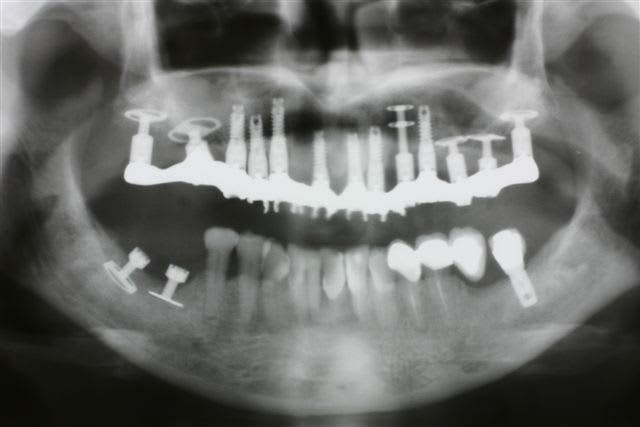

J'ai attentivement regardé ton cas , notamment au max... je trouve impressionnant le nombre d'implant que tu mets...

pour une arcade complète... 13 pour le haut... je penses que 10 suffisent largement... peux tu expliquer ce choix? et deuxième point comment explique tu le problème gingival entre 12 et 11?

C'est vraiment pour le débat, parce que autrement ta gestion de l’Échec mand est vraiment top et comme tu as une philosophie de traitement différente de la mienne, j'aime bien comprendre les raisonnements des autres...ça aide a avancer...

Premier précepte de l implanto basale : tjs duu fixe

Deuxième précepte de l implanto basqle : tjs des ancrages postérieurs donc on va loin au bout des max et mand même si tu peux trouver ça inutile ds un premier tps

Troisième précepte de l implanto basale : qd les volumes sont réduits comme ici où tout le secteur distal est en mono disk ou pire même en plaque, on augmente le nombre d implants au max pour répartir les forces... Il ne faut jamais perdre de vue que même si c est très solide une fois intégré, on passe par la MCI où la solidité est précaire au début...